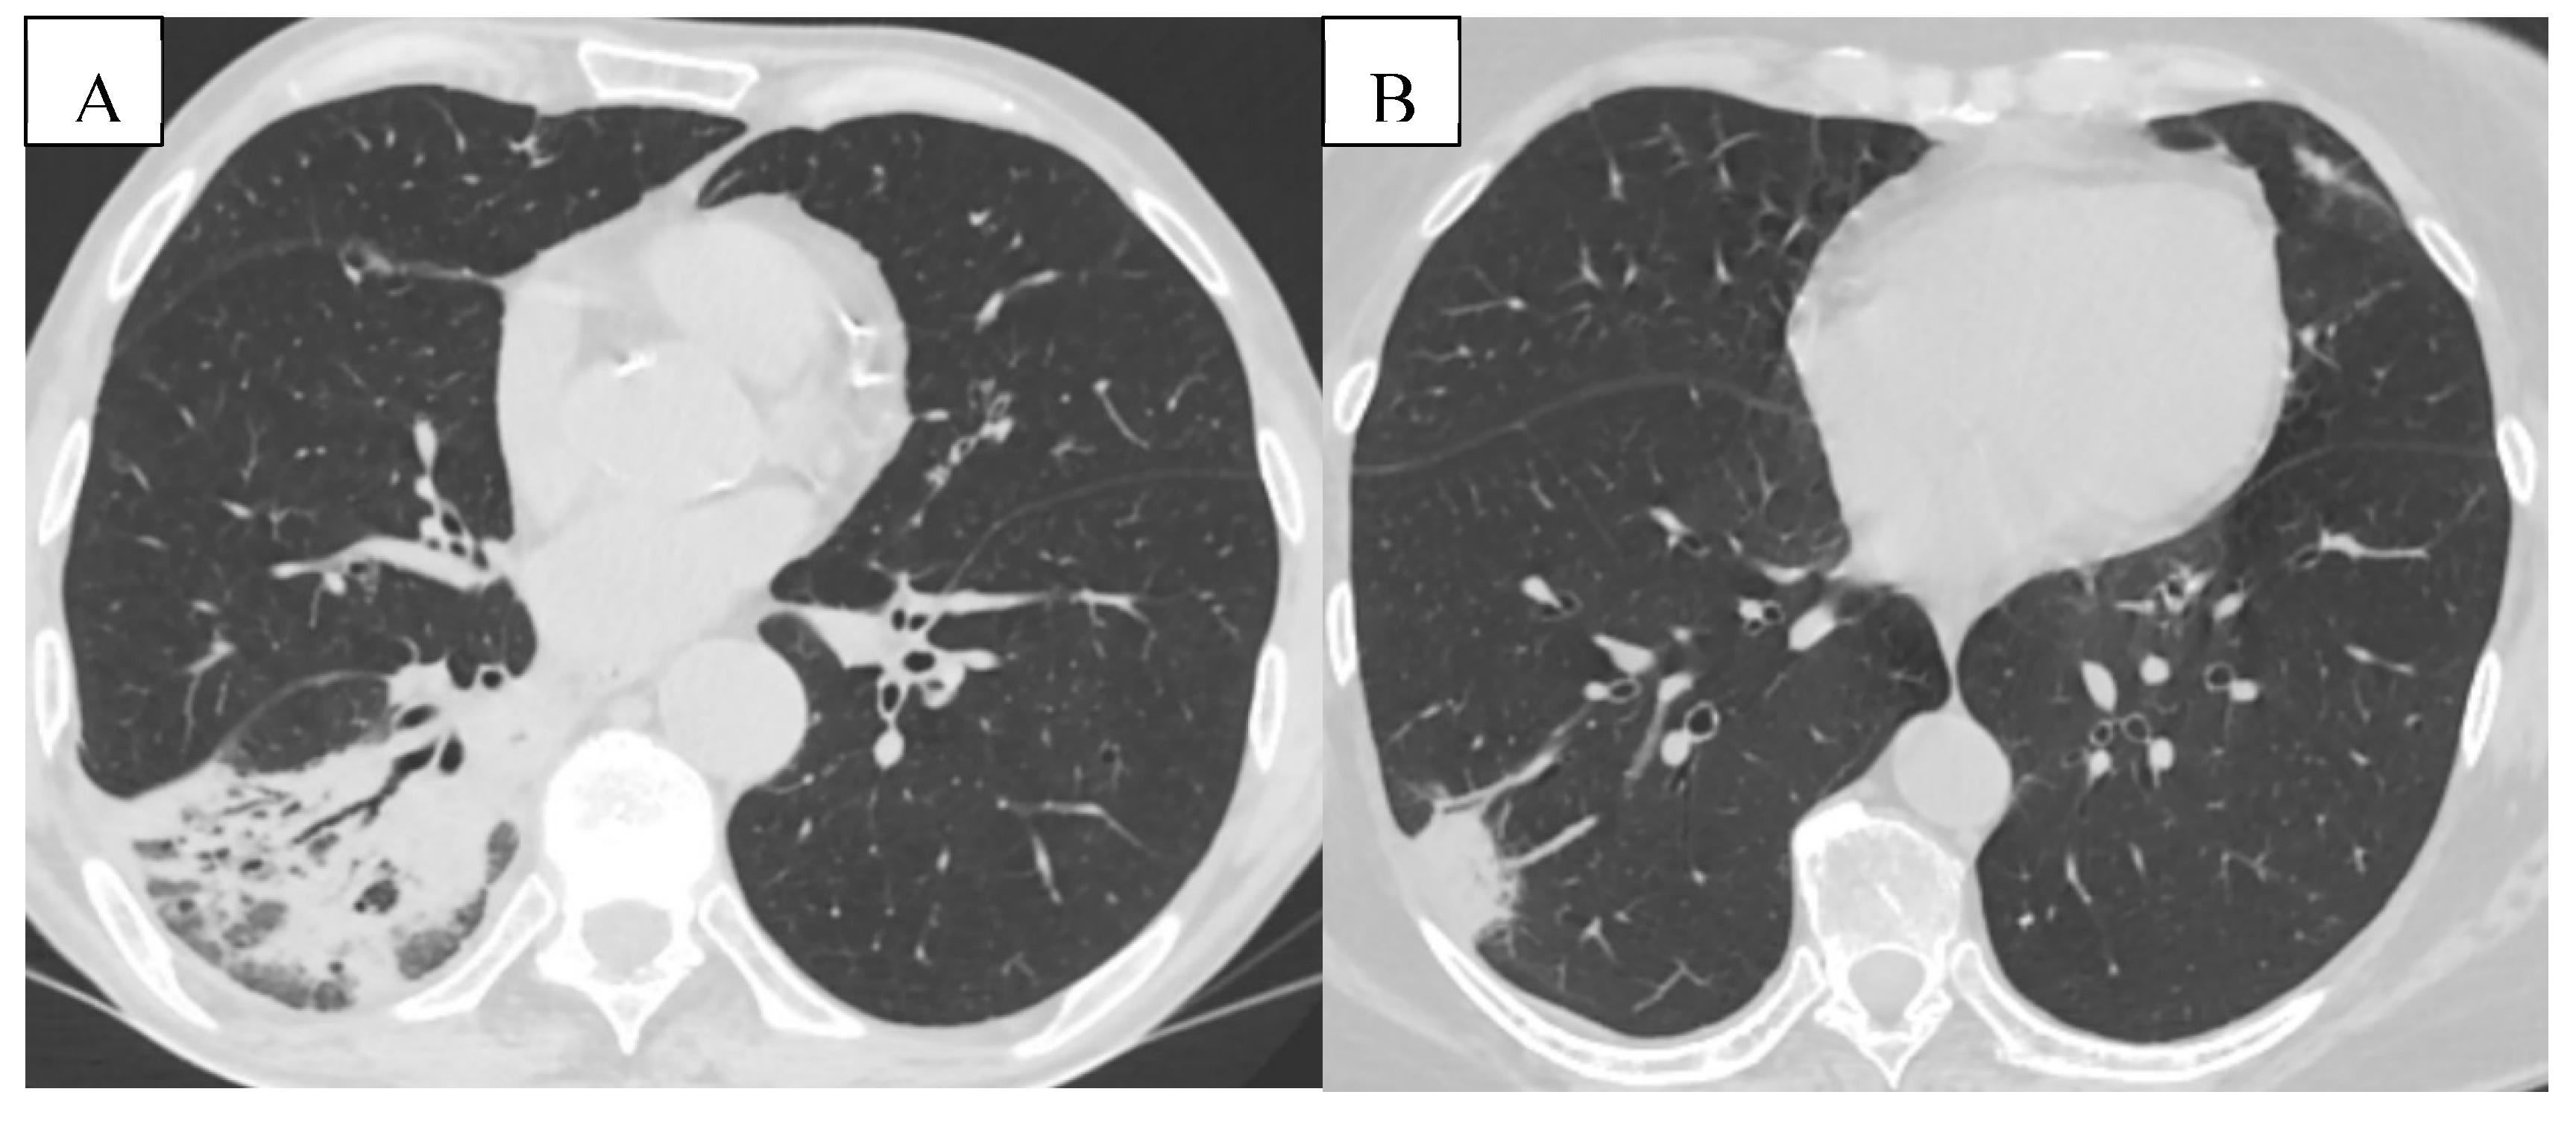

Detailed HRCT examples of emphysema morphology and bronchial stenosis are presented in Figure 5.

As depicted in Figure 6, chest CT further revealed a wide spectrum of comorbidities, including bronchiectasis, pulmonary artery enlargement, osteoporosis, and interstitial lung disease.

Lung cancer is the second most common malignancy worldwide, resulting in one-quarter of all cancer-related deaths. Patients with COPD have a 2- to 6-fold increased risk of developing lung cancer compared to smokers without airflow limitation. [42] In this study, lung cancer (pulmonary nodules or pulmonary masses) was found in 14% of cases. In a prospective cohort study involving over 2,000 participants with COPD, the 10-year cumulative incidence of lung cancer was approximately 16–20%, particularly in those with emphysema-dominant phenotypes and GOLD stage III/IV airflow limitation. [43] CT with virtual bronchoscopy (VB) has been found to be very helpful in defining the location, extent, and nature of these lesions, and is increasingly being used even in patients with contraindications for fiberoptic bronchoscopy and laryngoscopy. VB is one of the most recently developed interactive 3D techniques applicable to the tracheobronchial tree. [44] The presence of emphysema, interstitial abnormalities, or both are significant risk factors for future lung cancer development in COPD patients.[45]

Figure 5. (A) Mixed bilateral pulmonary emphysema (paraseptal and centrilobular emphysematous bullae). (B) Peripheral nodular formation in the lower lobe of the right lung. Mixed bilateral pulmonary emphysema. (C) Central tumoral mass of the right lung with invasion of the main bronchi bilaterally and lobar branches B4, B5 on the right. (D,E) Virtual bronchoscopy, presence of extrinsic stenosis of the main bronchi bilaterally.